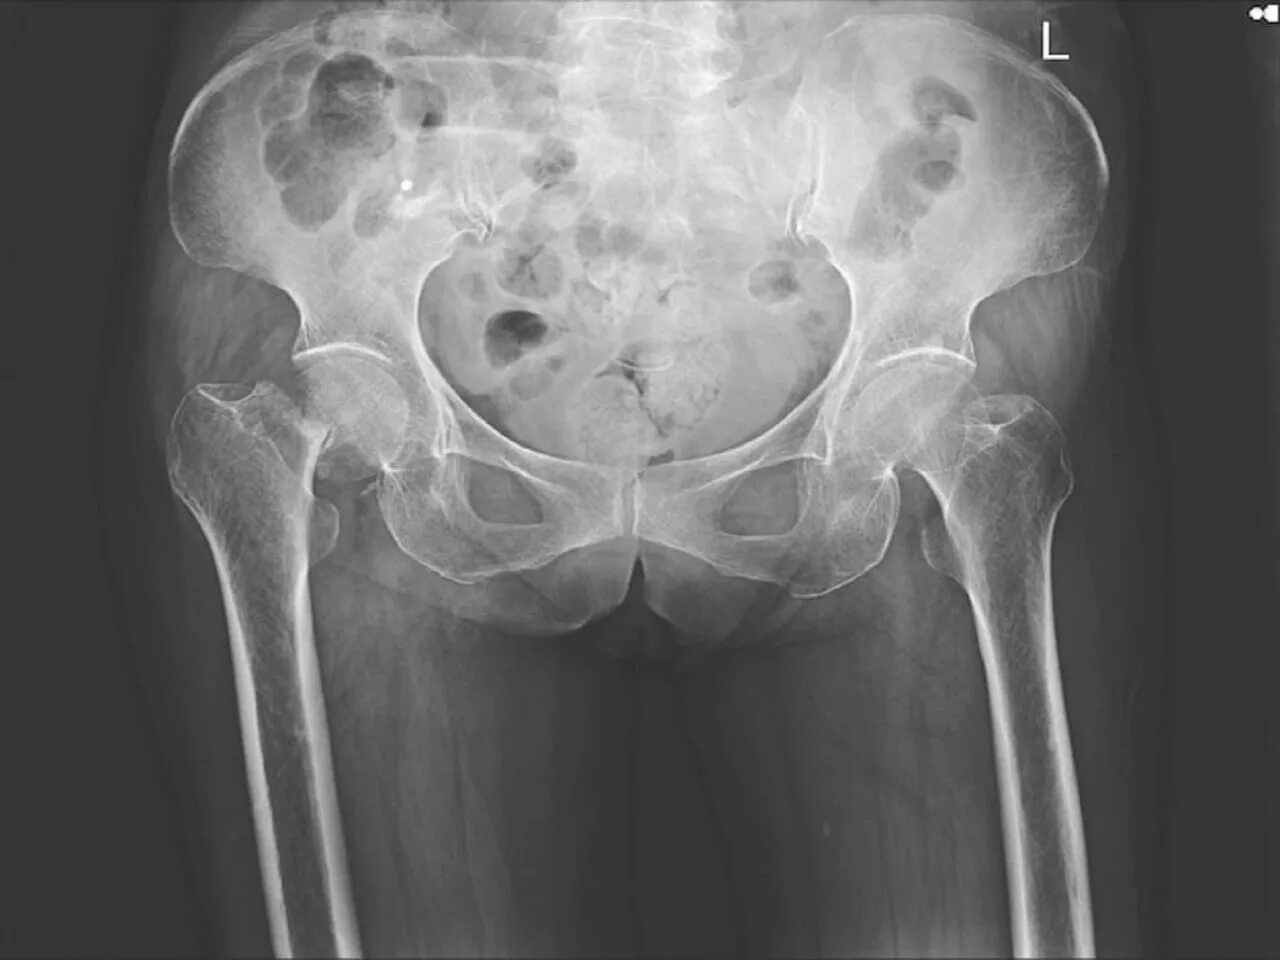

Метастазы в тазобедренном суставе